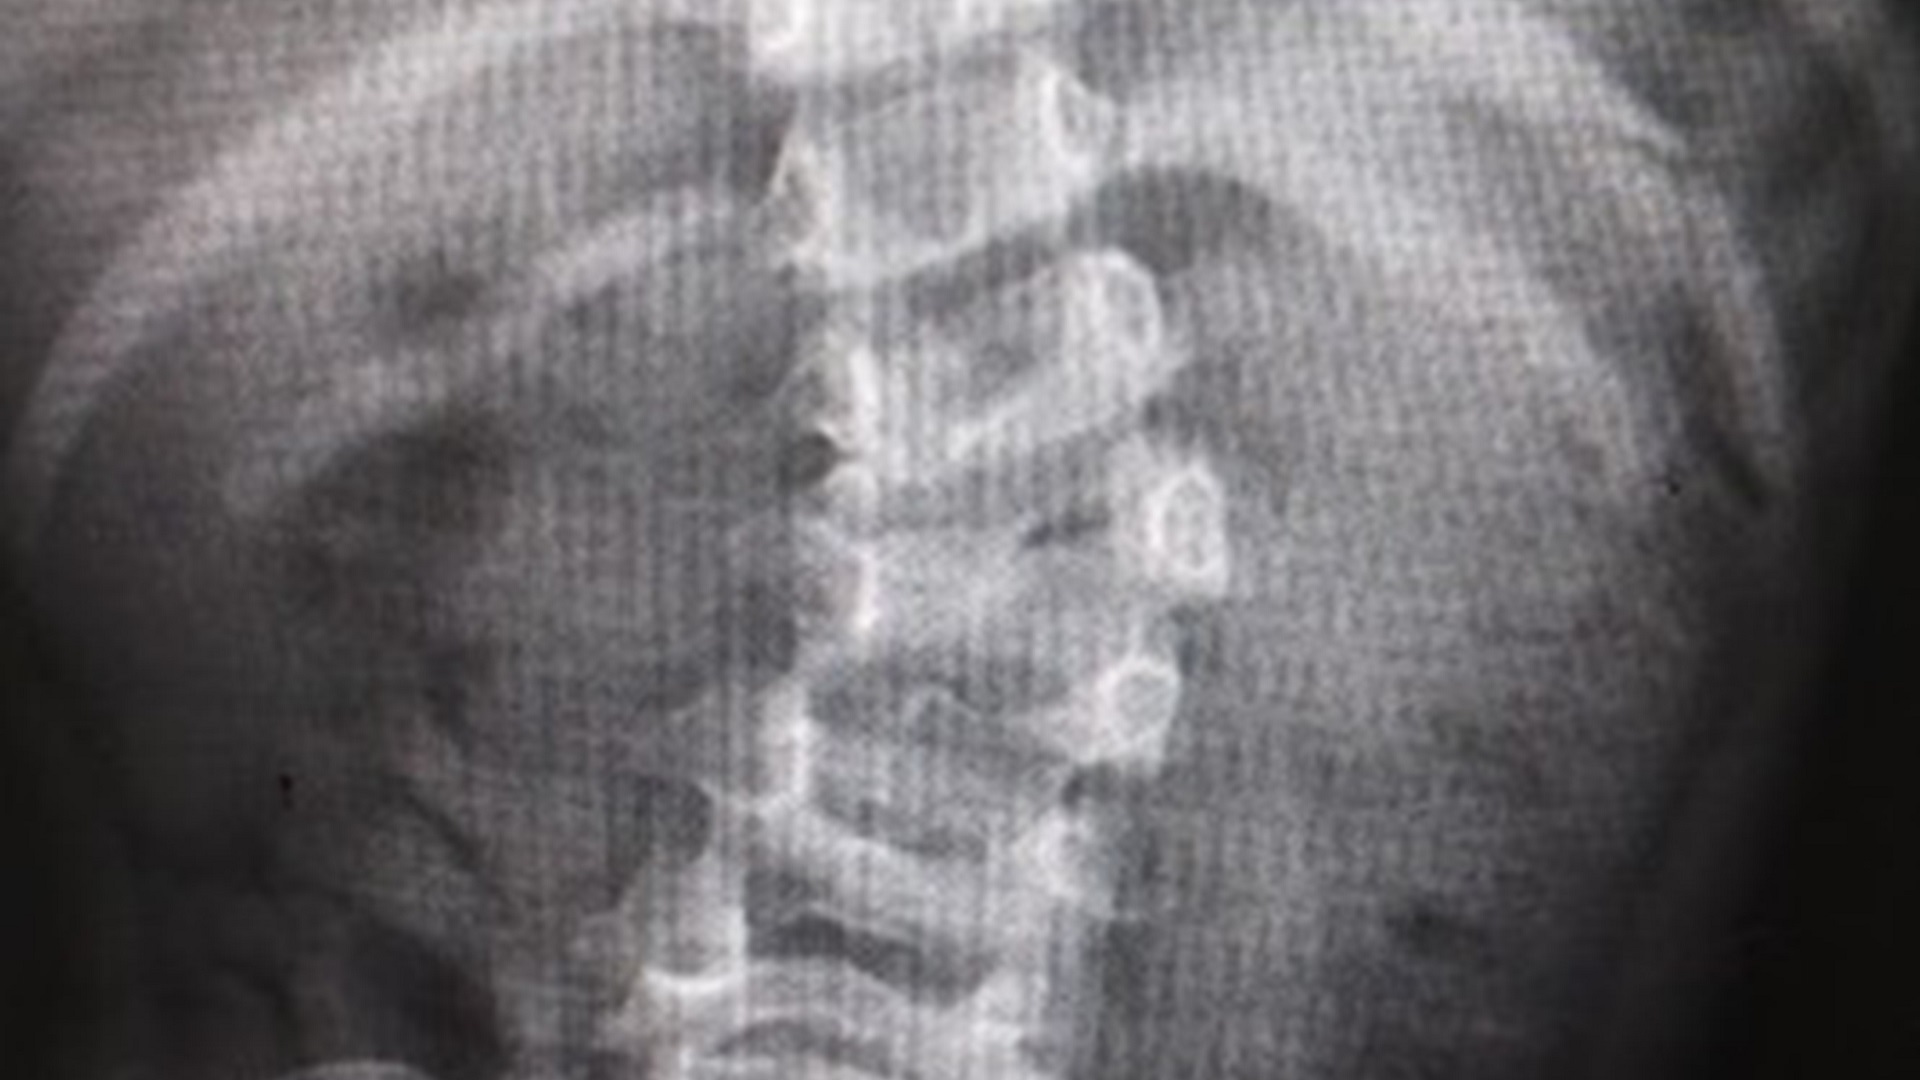

Corrigen malformación de columna a niña de 4 años en el IMSS - escoliosis-congenita

Escoliosis congénita. Foto de IMSS

Fátima nació con escoliosis congénita, lo que provocó que su columna vertebral creciera en forma de ‘S’ y que en consecuencia sus hombros y caderas estuvieran desnivelados.